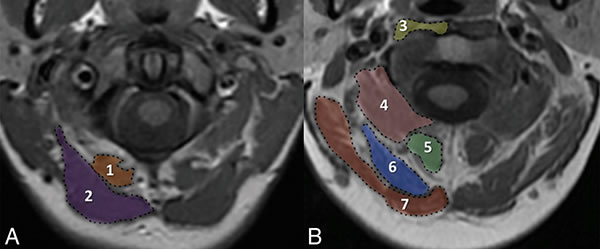

Магнитно-резонансная томография подзатылочных (субокципитальных) мышц. Мышцы на уровне передней дуги позвонка С1 (A): 1 - малая задняя прямая мышца головы, 2 - большая задняя прямая мышца головы. Мышцы на уровне середины зубовидного отростка С2 позвонка (B): 3 - длинная мышца шеи/головы, 4 - нижняя косая мышца головы, 5 - полуостистая мышца шеи, 6 - полуостистая мышца головы, 7 - ременная мышца головы.